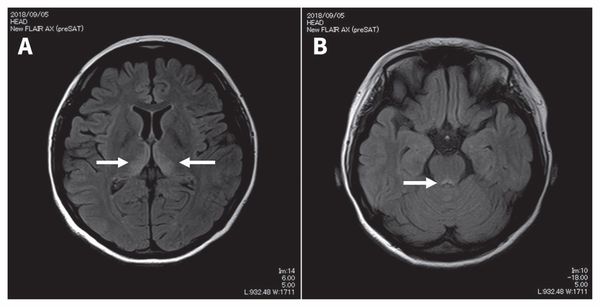

![Признаки энцефалопатии Вернике на снимке МРТ [22]](/pimg3/prognoz-lechenie-alkogolnoy-D2F68F.jpeg)

Может применяться компьютерная томография (КТ) и магнитно-резонансная томография (МРТ). С помощью КТ определяют участки пониженной плотности в центральном сером веществе среднего мозга и в части таламуса, но в большинстве случаев этот метод не выявляет очаговой патологии при острой энцефалопатии.

Наиболее эффективный метод диагностики энцефалопатии Вернике — это МРТ. Интерпретировать результаты МРТ сможет только врач.

В половине случаев синдром Гайе-Вернике сопровождается генерализованным замедлением волн при ЭЭГ. РЭГ зачастую определяет диффузное снижение церебрального кровотока. КТ головного мозга, как правило, не регистрирует патологические изменения в церебральных тканях. МРТ головного мозга позволяет выявить гиперинтенсивные области в медиальных ядрах таламуса, мамиллярных тельцах, стенках III желудочка, ретикулярной формации, сером веществе, окружающем сильвиев водопровод, крыше среднего мозга. Зоны поражения склонны накапливать контраст, вводимый при проведении дополнительного контрастирования в ходе МРТ. В перечисленных областях могут определяться петехиальные кровоизлияния и признаки цитотоксического отека.